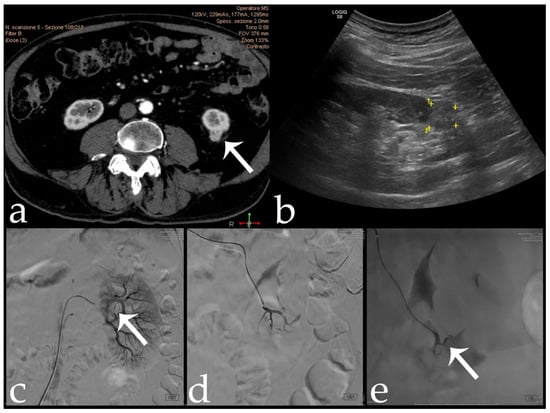

Figure 3. 80 yr old male with intra-cortical RCC of the left kidney lower pole (15 × 15 mm) (arrows): (a,b) pre-operative CECT and US; (c) pre-embolization angiographic study; (d,e) post-embolization control after 18-Onyx and indocyanine mixture administration.